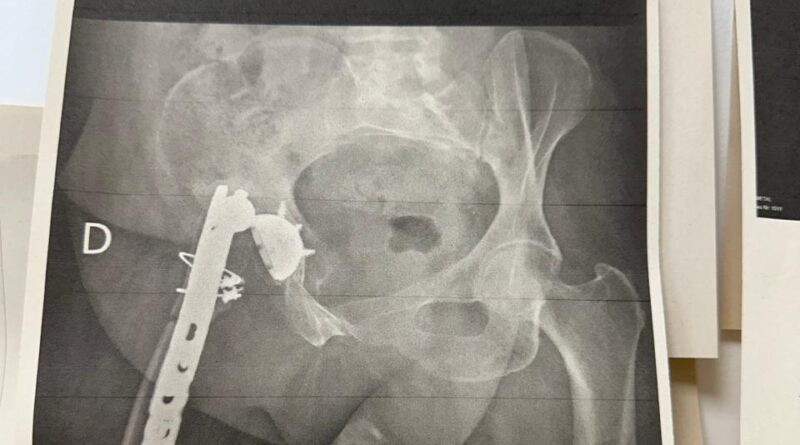

O Hospital Ortopédico do Estado da Bahia (HOEB), unidade da Secretaria da Saúde do Estado (Sesab) administrada pelo Einstein, realizou nesta segunda-feira (3) mais um transplante de tecido musculoesquelético. O órgão veio de um banco de ossos no Rio de Janeiro. A paciente, uma mulher de 53 anos, da região de Feira de Santana, precisou fazer a troca de uma prótese de quadril.